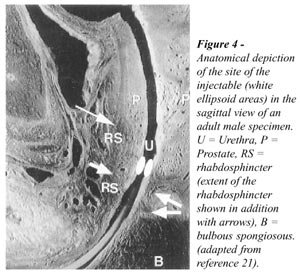

Usually patients where the rhabdosphincter

mucosa from the level of the external sphincter cranially (Figure-4).